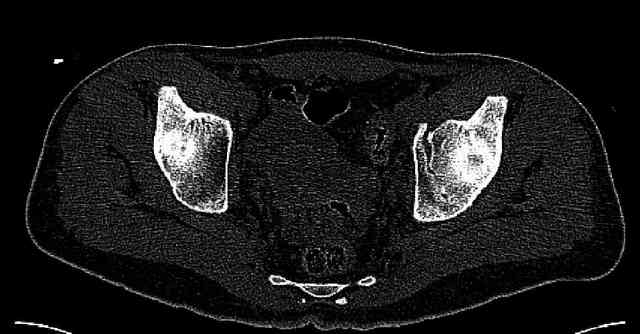

Re: Нелеченный перелом вертлужной впадины

Some more images. Does it help to guess which part of the acetabulum is displaced?